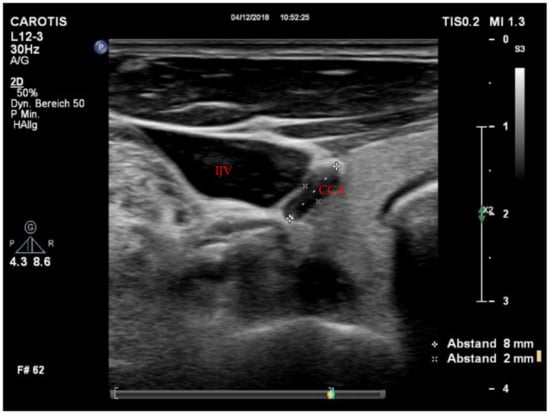

Figure 2. Collapse of the CCA during hypovolemic CA. CCA = common carotid artery; CPR = cardiopulmonary resuscitation; IJV = internal jugular vein.

Utilizable US images were acquired in 14 cases (88%), and we completed the full imaging protocol in 11 patients (69%). Of those, five (63%) were measured during conventional CPR, four (25%) immediately after ROSC, and two (12%) during ECPR. All patients with incomplete imaging protocols were assessed during conventional CPR. There were no significant differences in peak systolic velocity (PSV) or enddiastolic velocity (EDV) between CPR, ECPR and ROSC cases. However, a trend towards higher values of EDV during ECPR could be shown (Table 1). In the comparison of flow velocities, only participants with completed imaging protocols were included. Concerning potential findings of clinical value, we detected a forward-flow during compression with a reverse flow during decompression in two cases (Figure 1) and a collapse of the CCA in one case (Figure 2). Videos of images of interest can be found in the Supplemental Material.

4.2. Carotid Artery Collapse

A collapse of the CCA in a patient with hypovolemic CA was observed (Figure 2). Due to the very small diameter of the collapsed vessel, we were unable to acquire valid velocity measures—however, in past animal studies, a CCA collapse was detrimental to carotid blood flow [19]. Furthermore, it has been shown that higher blood flow velocities are associated with a higher invasive blood pressure [20]. In line with this, dynamics of the PSV in the CCA have been shown to be sensitive and specific to determine volume responsiveness in septic shock [21]. Similarly, we recorded a rise in PSV during ECPR after the additional initiation of continuous vasopressor support. These findings suggest that carotid US could be useful to determine hypovolemic origin of cardiac arrest and may guide volume resuscitation during CPR.

The following are available online at https://www.mdpi.com/article/10.3390/jcm11020469/s1. Video S1. Transverse view of the CCA (image right) and IJV (image left). The CCA is collapsed independent of compression while the vein remains compressible. The cause of the patients CA was hypovolemia due to pulmonary bleeding. CCA = common carotid artery; IVJ = internal jugular vein; CA = cardiac arrest. Video S2. Coronal view of the CCA with colour doppler. The vessel shows forward flow during compression and reverse flow during decompression. Note that there are no signs of aliasing. CCA = common carotid artery Video S3. Coronal view of the CCA with colour doppler. The vessel shows continuous forward flow with minimal variation. The loop was recorded shortly after the patient regained circulation during eCPR. CCA = common carotid artery.